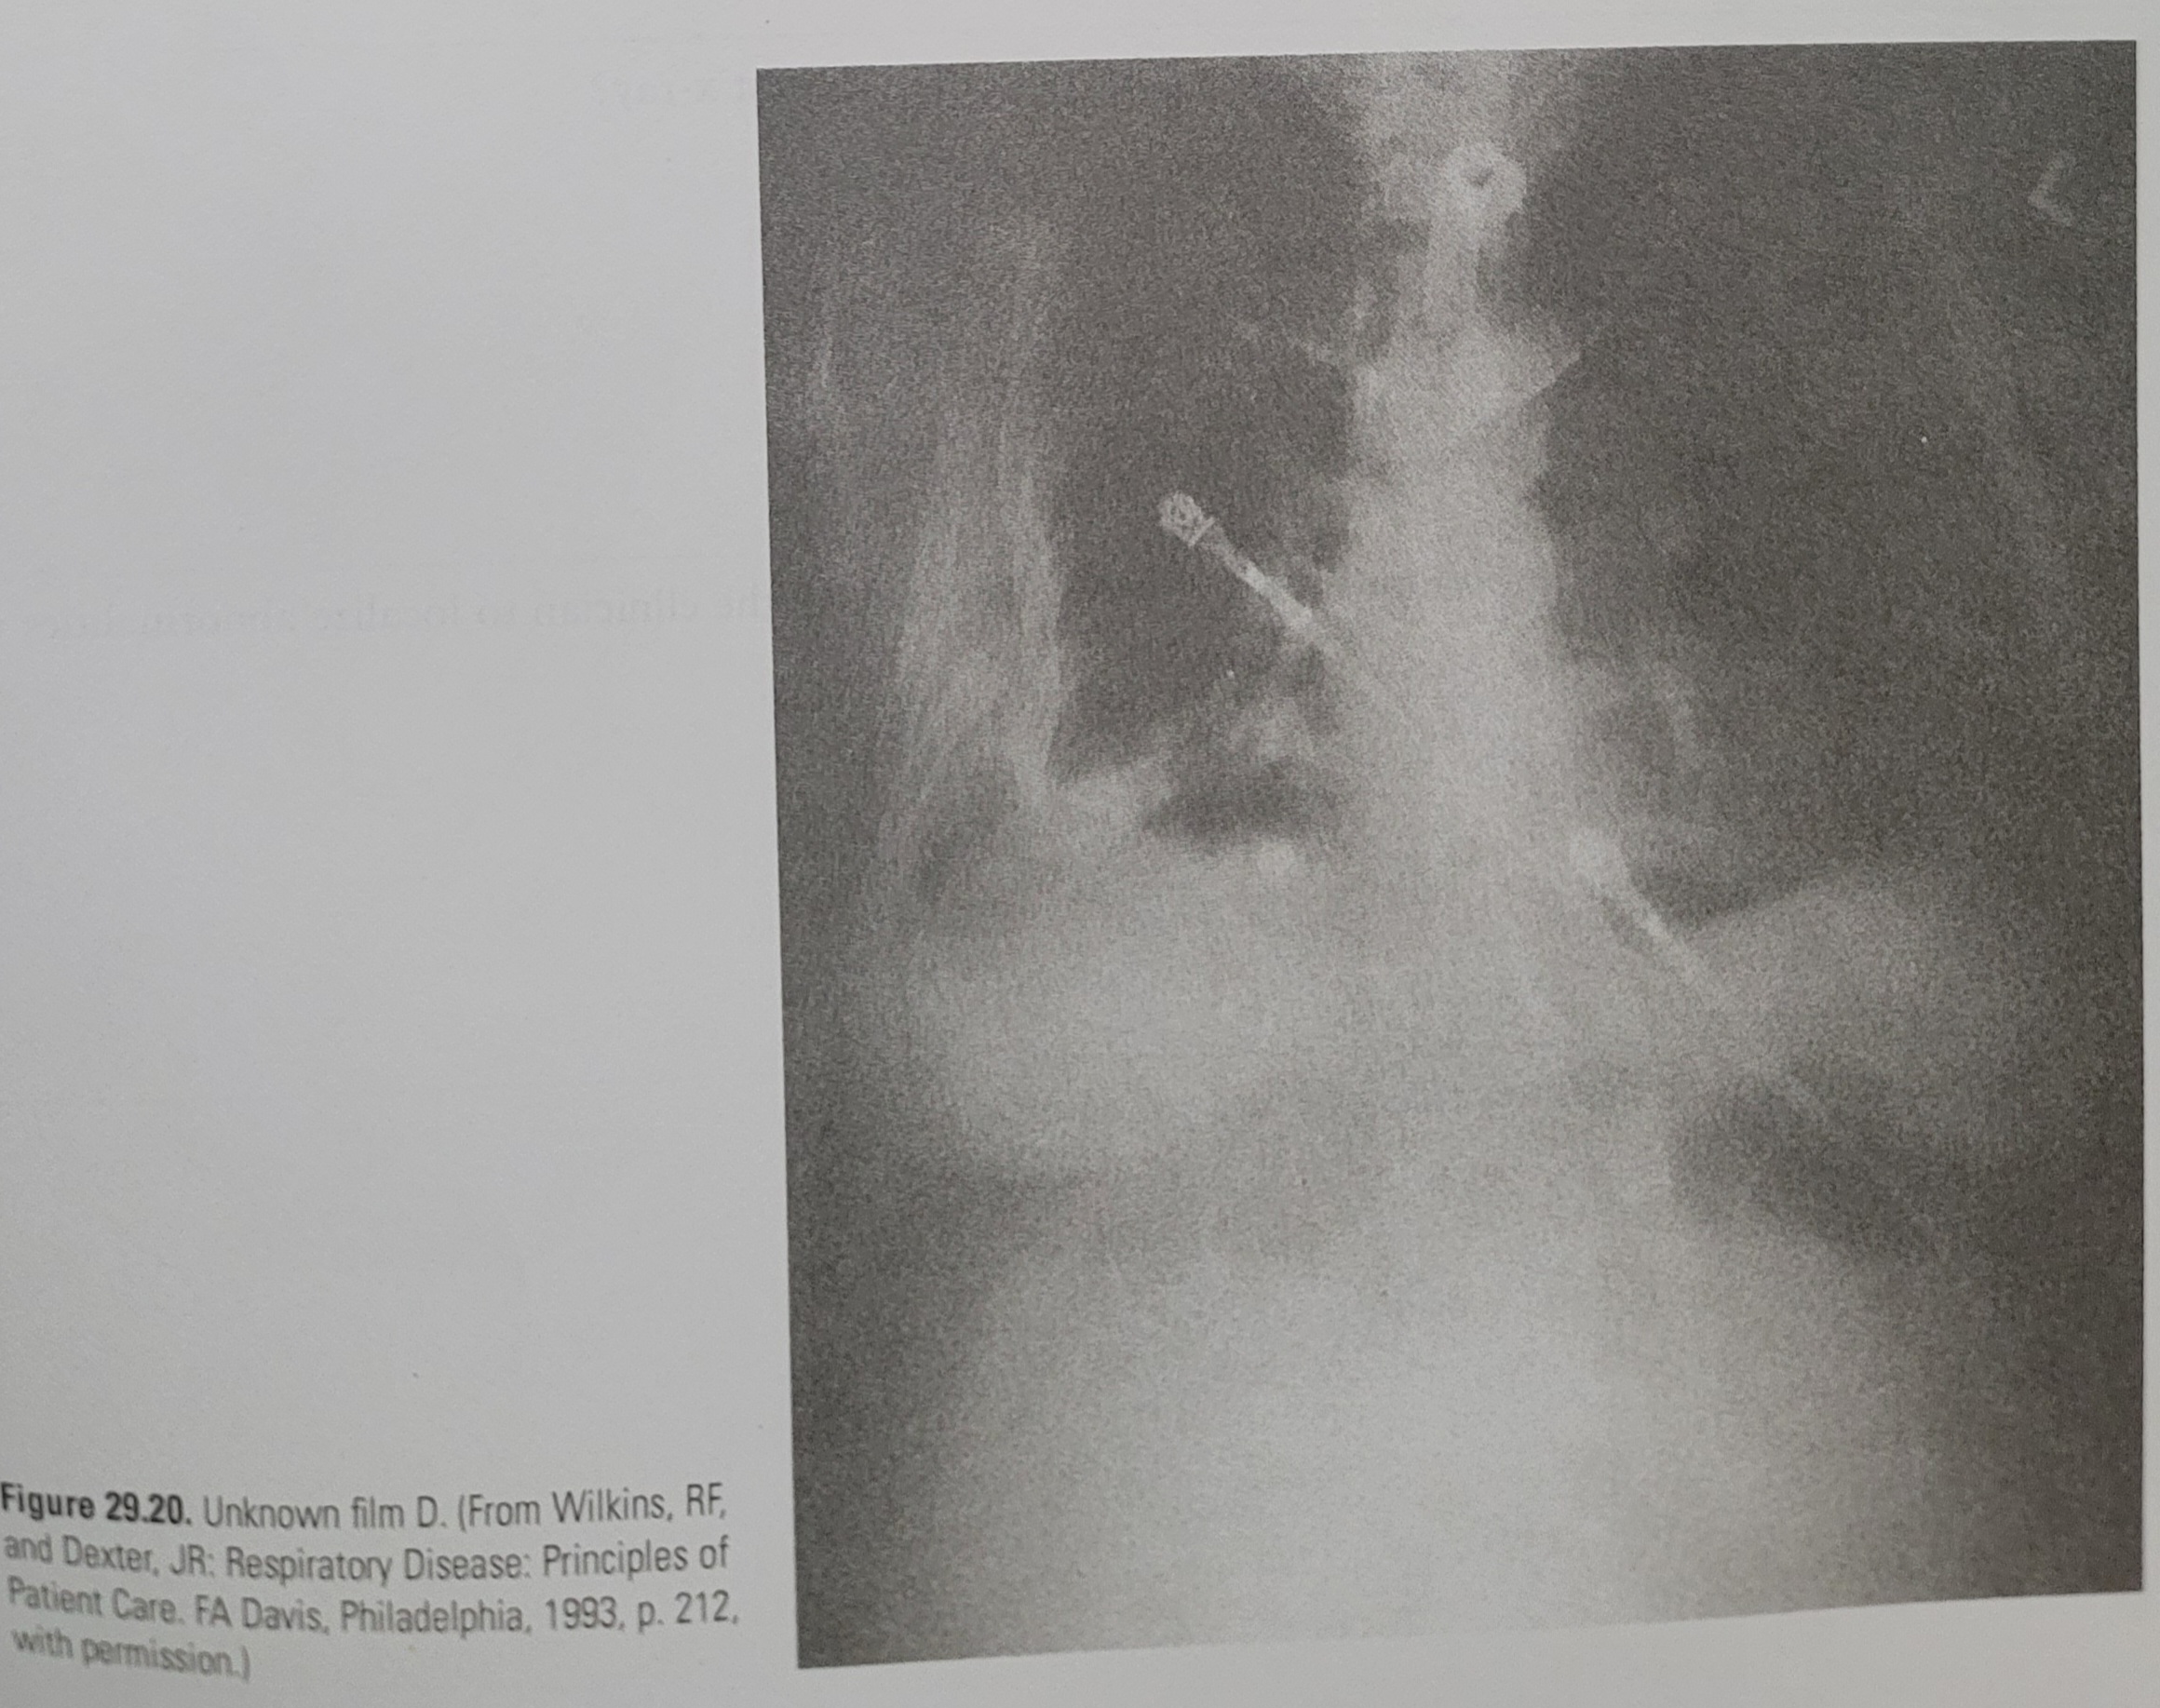

Image gallery of Terminal Mystery: The Patient With The Unknown Blue Triangular Pill